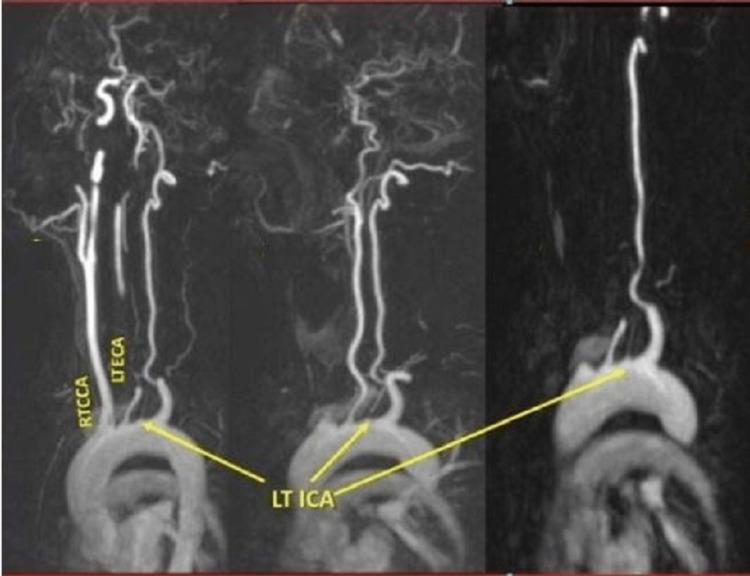

The agenesis of the left common carotid artery, with independent origins of the external and internal carotid arteries from the aortic arch, is a well-described but extremely rare congenital anomaly. We present a case of agenesis of the left common carotid artery with the independent origin of the left internal and left external arteries from the arch of the aorta in a patient with ankylosing spondylitis which was depicted by CT angiogram and magnetic resonance angiography. The diagnosis of this anatomical variant especially before interventional procedures is of great importance, as it could complicate the catheterization of these arteries.

左颈总动脉缺如,颈外动脉和颈内动脉分别独立起自主动脉弓,是一种已被充分描述但极为罕见的先天性异常。我们报告一例患有强直性脊柱炎的患者,其左颈总动脉缺如,左颈内动脉和左颈外动脉分别独立起自主动脉弓,通过CT血管造影和磁共振血管造影得以显示。诊断这种解剖变异,尤其是在进行介入操作之前,非常重要,因为这可能会使这些动脉的插管复杂化。